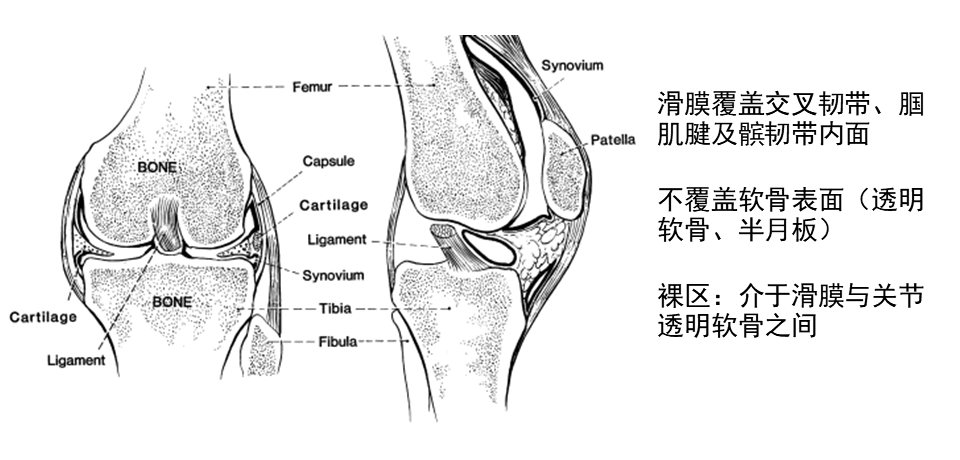

膝关节滑膜解剖

膝关节滑膜是覆盖于关节囊内面并构成关节囊内层的一层薄膜,具有分泌滑液、润滑关节、营养关节软骨等功能。在膝关节内,滑膜覆盖交叉韧带、腘肌腱以及半月板之下的冠状隐窝等结构,同时,髌韧带内面也有滑膜覆盖。关节软骨和半月板处无滑膜。滑膜内含有丰富的血管和神经,对关节的生理功能和病理变化起着重要作用。

正常滑膜,影像不能显示。滑膜增厚,伴有关节腔积液时,可显示滑膜。增强扫描可直接显示增厚的滑膜。